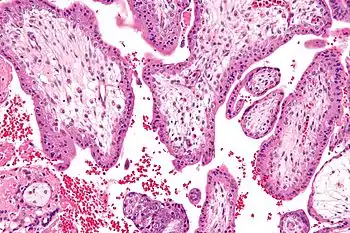

Micrograph showing chorionic villi - the tissue that is collected in CVS. H&E stain. | |